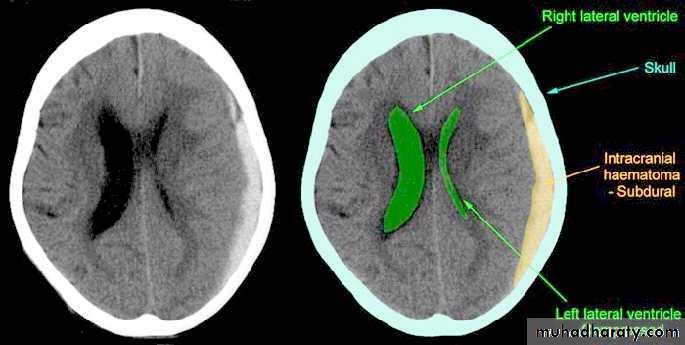

b. Subdural Haematoma

They are the most common intracranial mass lesions resulting from head trauma.

They are classified depending on how long they take to present clinically following the injury into:

Acute Subdural Haematoma: less than 3 days

Subacute Subdural Haematoma: 4-21 days

Chronic Subdural Haematoma more than 21 days.

Acute Subdural Haematoma

Usually due to MORE SEVER high velocity trauma and thus associated with a poorer outcome.

Clinical Picture: patient will present with a picture similar to that of an extradural haematoma, but there is persistent loss of consciousness with no lucid interval.

Ct scan will show a concave hyperdence collection because blood follows the subdural space over the convexity of the brain.

Acute Subdural Haematoma are rapidly evolving lesions and early evacuation via craniotomy is mandatory.